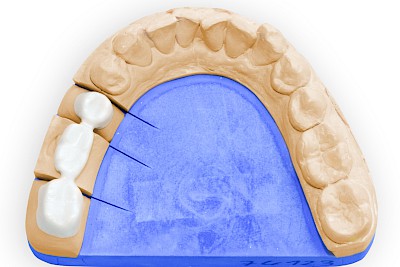

Material von (Teil-)Kronen & Brücken

- Goldhaltige oder edelmetallfreie Legierungen: gold- bzw. silberfarben

- Legierungen verblendet mit Kunststoffen: zahnfarben (v. a. früher)

- Legierungen verblendet mit Keramik: zahnfarben

- Vollkeramische Kronen & Brücken: zahnfarben

Teilweise werden Füllungen oder auch Kronen (vor allem an den Rändern) nach und nach ergänzt oder nur teilweise ausgetauscht. Dann kann es sein, dass an Zähnen verschiedenen Materialien zum Einsatz kommen.